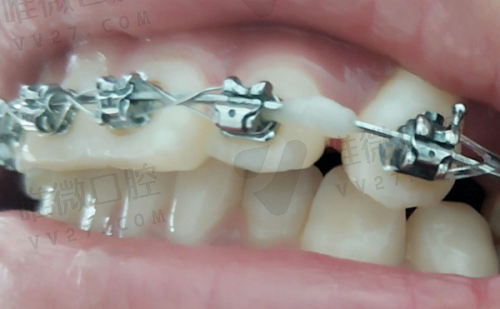

- 传统金属托槽矫正

- 陶瓷托槽矫正

- 舌侧矫正